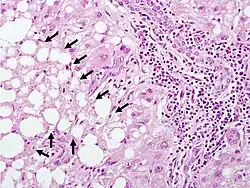

The second phase occurs between 24 hours and 72 hours following overdose and consists of signs of increasing liver damage. In general, damage occurs in liver cells as they metabolize the paracetamol. Hallmark pathology on liver biopsy includes regions of coagulative necrosis in zone 3 of the liver acinus, around the central venules, as these hepatocytes have higher concentrations of cytochrome P450 enzymes compared to zone 1 hepatocytes surrounding the portal venule of the acinus. Remaining viable hepatocytes frequently show ballooning injury and steatosis.[13] The individual may experience right upper quadrant abdominal pain. The increasing liver damage also changes biochemical markers of liver function; International normalized ratio (INR) and the liver transaminases ALT and AST rise to abnormal levels.[14] Acute kidney failure may also occur during this phase, typically caused by either hepatorenal syndrome or multiple organ dysfunction syndrome. In some cases, acute kidney failure may be the primary clinical manifestation of toxicity. In these cases, it has been suggested that the toxic metabolite is produced more in the kidneys than in the liver.[15]